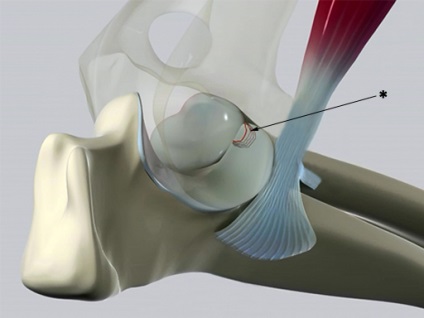

DLS kezelés lehet konzervatív és operatív, a taktika mindig egyéni, és függ az oka a diszplázia és a mértéke annak súlyosságát. Az eljárás nyílt utat, és arthroscopically. Vannak különböző üzemi berendezések artroszkópos eltávolítása patológiás fragmens osteotomia koronoid, proximális ulna osteotomia, kimetszés disztális biceps ín a kapcsolódási pont a ulna, stb Súlyos esetekben, lehet teljes arthroplasztikai a könyökízület .. Jelenleg a DLS gyűjt statisztikai adatokat, és a betegség, kivéve a súlyos formák, ez nem egy szigorú jelzéssel selejtezésre, de még mindig ajánlott, hogy megakadályozza kutyák patológia tenyésztésre, mivel azok át egy örökletes vonalat. A közös minősül rendellenes működését, ha megerősítette radiológiailag destruktív ízületi változásokat ismertetjük.